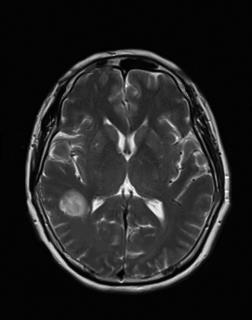

• 肿瘤样脱髓鞘病变报道3例

2023, 48(5):614-617. DOI: 10.13406/j.cnki.cyxb.003183

摘要 (95) HTML (24) PDF 1.29 M (241) 评论 (0) 收藏

摘要: